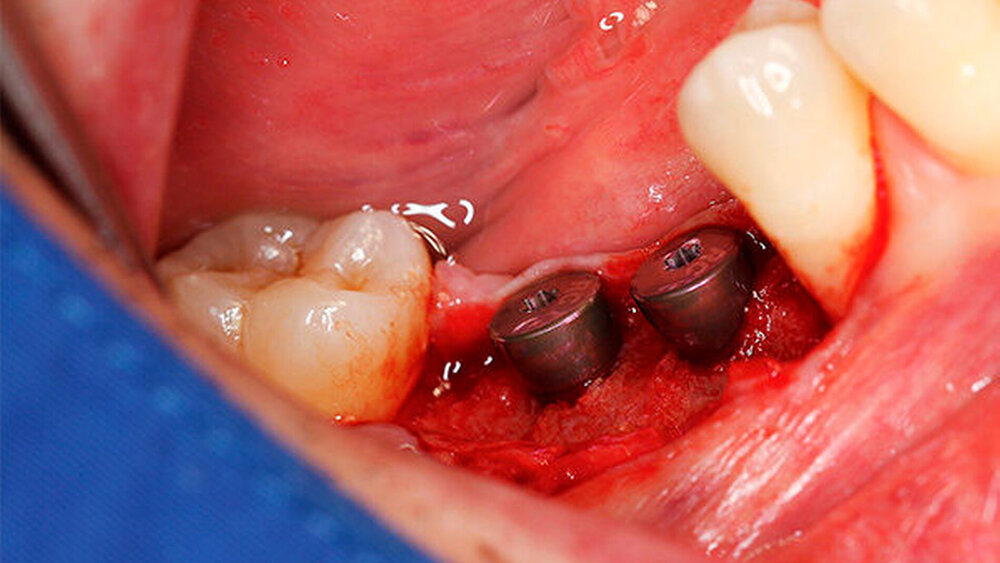

Die Schnittführung wurde nach dem Pillar-Sockel-Design (Blume) vorgenommen. Dabei liegt die Inzision weit im Vestibulum und verbindet zwei vertikale Entlastungsschnitte. Im Gegensatz zu der herkömmlichen krestalen Schnittführung bleibt das Periost über dem augmentierten Bereich damit völlig intakt. Nach der streng subperiostalen Präparation erfolgte die Kontrolle der Passung des CAD/CAM-Blocks. Ein ganz entscheidender Punkt ist, vor jeglichem Kontakt des Blockes mit Blut diesen in steriler Kochsalzlösung und am besten in der PRF-Flüssigkeit zu wässern, sodass sich keine Poren des Blocks mit Blutkoageln verschließen und innerhalb des Blocks ein nicht mit Blut gefüllter Hohlraum bildet. Vor der Befestigung des Blocks wurde die Kompakta des Empfängerbetts mit einer kleinen Kugelfräse mehrfach perforiert um sogenannte Bleeding Points zu setzen, die die Durchblutung des Knochenblocks gewährleisten. Mit zwei Osteosyntheseschrauben mit dem Durchmesser 1,5 mm und der Länge 9 mm wurde der allogene Knochenblock rotationssicher fixiert. Das Augmentat wurde mit einer dünnen Schweinepericard-Membran (Jason membrane, botiss biomaterials GmbH, Vertrieb Straumann) und der PRF-Membran abgedeckt. Der spannungsfreie Wundverschluss erfolgte mit der modifizierten vertikalen Matratzennaht nach Laurrell mit resorbierbarem Nahtmaterial (Vicryl 4.0). Postoperativ wurde ein Oberkiefer-DVT angefertigt. Die Nahtentfernung wurde im Rahmen der Nachsorgeuntersuchung sieben und 14 Tage postoperativ vorgenommen. Nach einer Heilzeit von sechs Monaten erfolgte die Implantation in Lokalanästhesie unter antibiotischer Abschirmung mit 2 g Amoxicillin oral eine Stunde präoperativ. Die Schnittführung erfolgte krestal, und nach subperiostaler Präparation wurde der Knochenblock dargestellt und die Osteosyntheseschrauben wurden entfernt. Danach wurden drei Implantate (Straumann) in den Knochenblock gesetzt und mit 0er-Verschlussschrauben abgedeckt. Die Wundrandadaptation erfolgte mit resorbierbarem Nahtmaterial, das bei der Verlaufskontrolle sieben Tage postoperativ vollständig entfernt wurde. Nach dreimonatiger gedeckter Einheilung wurden die Implantate im Rahmen einer Vestibulumplastik freigelegt. Dafür wurde eine erneute krestale Schnittführung regio 14 bis 17 vorgenommen und ein Splitflap präpariert. Der vestibuläre Wundrand wurde mit Einzelknopfnähten im Vestibulum fixiert. Im Bereich der Implantate wurde der Splitflap perforiert, um die Abdeckschrauben gegen Gingivaformer auszutauschen, und der Bereich des nun freiliegenden Bindegewebes wurde mit einer 3D-vernetzten Kollagenmatrix (mucoderm, botiss biomaterials GmbH, Vertrieb Straumann) abgedeckt. Diese wurde zunächst gewässert, um die Verarbeitung zu erleichtern, und an den Stellen der Gingivaformer gestanzt. Die Nahtentfernung erfolgte neun Tage postoperativ. (Abb. 1a bis 1f).

Ein 29-jähriger Patient stellte sich mit einer massiven Alveolarkammatrophie im rechten Unterkiefer in unserer Praxis vor. Diese lag in langen Jahren der Zahnlosigkeit begründet. Eine Beckenkammaugmentation kam für den Patienten nicht in Betracht. Dennoch wünschte er die Versorgung mit festsitzendem Zahnersatz. Nach ausführlicher Beratung entschied sich auch dieser Patient für eine Augmentation mit einem patientenindividualisierten allogenen CAD/CAM-gefertigten Knochenblock. Die DICOM-Daten des Unterkiefer-DVTs wurde an die Firma Zimmer gesendet, und es erfolgten wie im oben beschriebenen Fall eine virtuelle Planung und das virtuelle Design des allogenen Knochenblocks anhand der geplanten Implantatpositionen. Nach der üblichen Kontrolle und Freigabe des Chirurgen erfolgte die eigentliche Fertigung und Übersendung des Knochenblocks in die Praxis. Die Augmentation erfolgte auch in diesem Fall in Vollnarkose unter antibiotischer Abschirmung perioperativ mit Ampicillin. Die Schnittführung im Unterkiefer unterscheidet sich von der Sockelschnittführung im Oberkiefer aufgrund der Anatomie (N. mentalis). Auch bei diesem Patienten wurde eine tief im Vestibulum liegende bogenförmige Inzi‧sion durchgeführt, jedoch ohne die vertikalen Entlastungen. Nach streng subperiostaler Präparation erfolgte die Darstellung des N. mentalis. Die Vorbereitung des Spenderbetts sowie die Wässerung, Einpassung und Befestigung des allogenen Knochenblocks gestalteten sich wie im Fallbeispiel 1. Die Heilzeit des Knochenblocks dauerte ebenfalls sechs Monate. Zwei Implantate (Straumann) wurden nach krestaler Schnittführung in Lokalanästhesie eingebracht und heilten subgingival binnen drei Monaten ein. Aufgrund des massiven Volumenzuwachses war auch ebenfalls eine Vestibulumplastik im Zuge der Implantatfreilegung notwendig. Das Prozedere verlief ebenfalls wie im Fallbeispiel 1. Das freiliegende Gewebe wurde mit einer Kollagenmatrix abgedeckt. Dadurch konnte die Breite der befestigten Gingiva deutlich verbreitert werden.